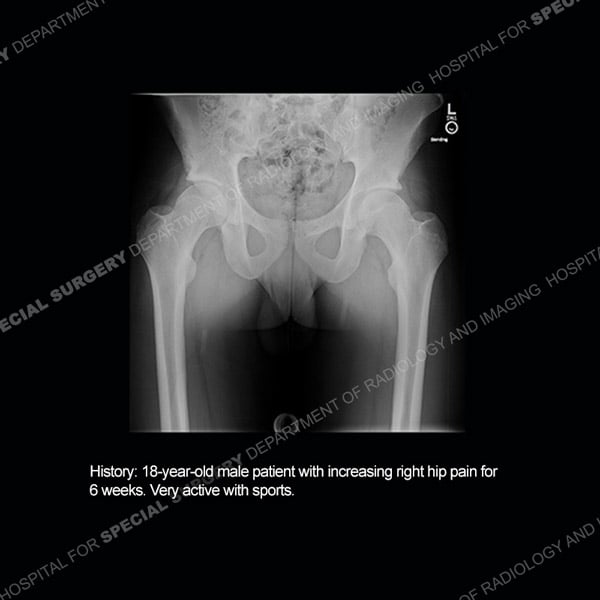

![]() |

Featured Case of the MonthCase 215: 85-year-old woman with recent exacerbation of left lateral hip pain.

|